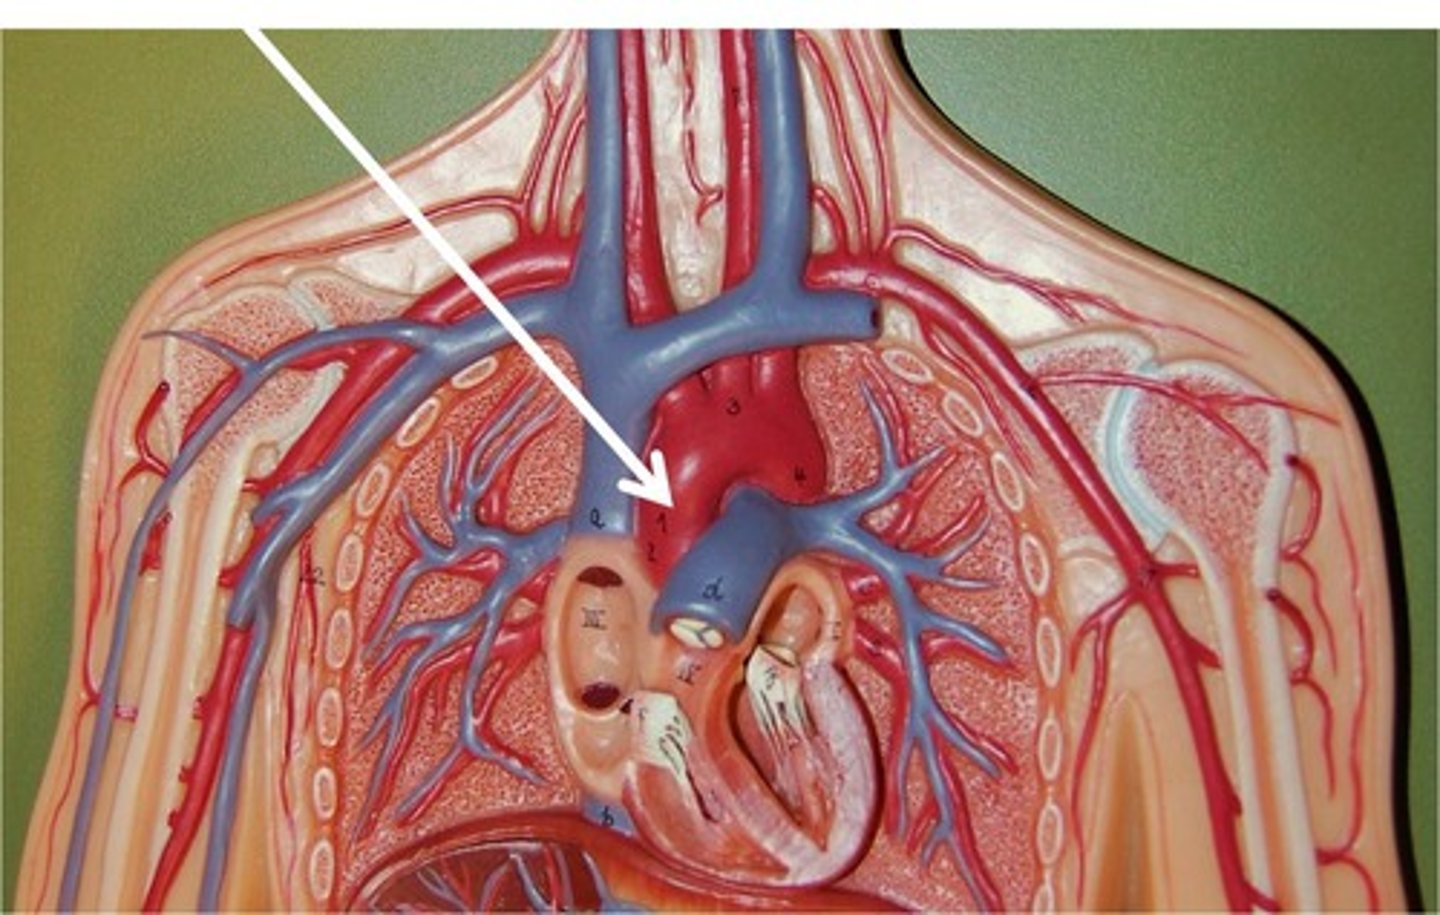

ascending aorta

branches include right and left coronary arteries

right coronary artery

left coronary artery

aortic arch

feeds brachiocephalic artery, right and left common carotid arteries, right and left subclavian arteries

brachiocephalic vein

superior vena cava